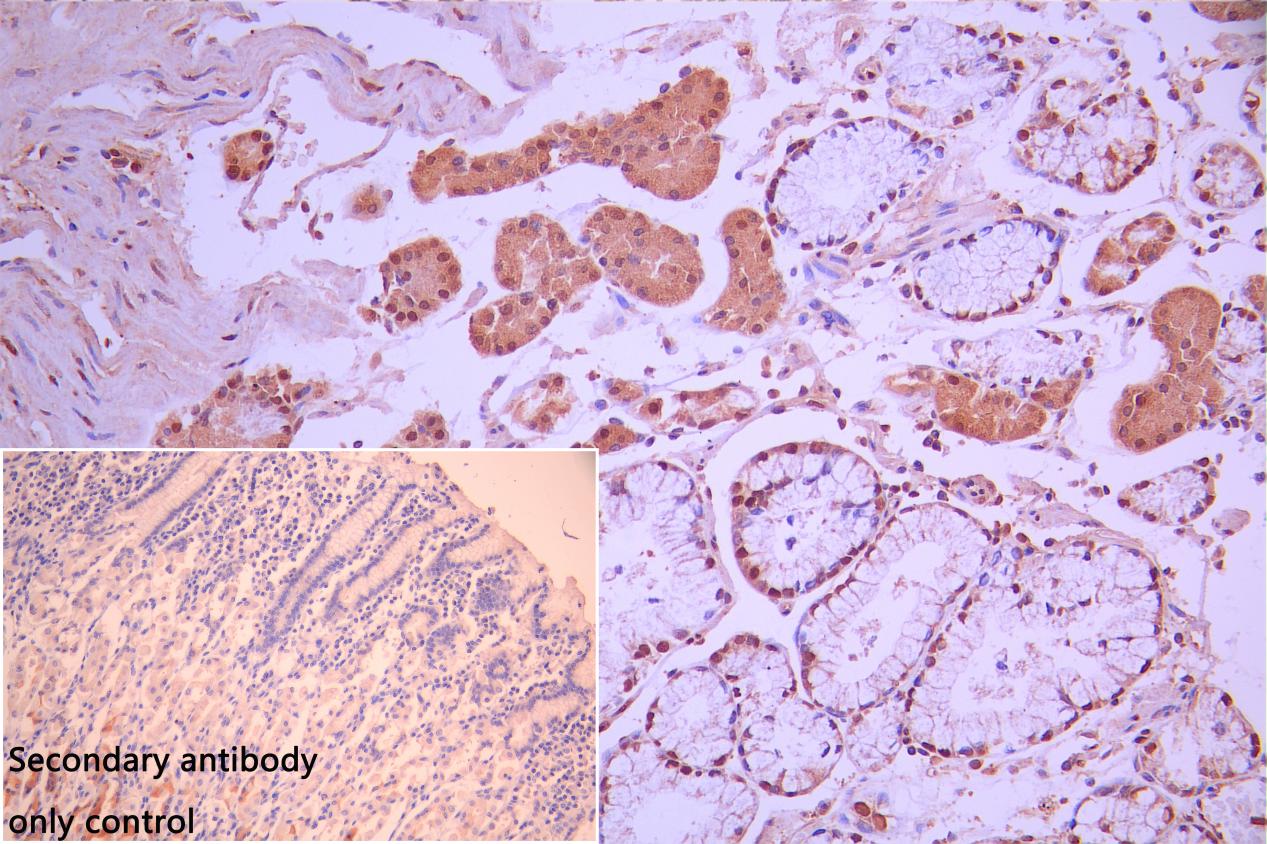

IHC image of CSB-PA023444LA01HU diluted at 1:100 and staining in paraffin-embedded human stomach tissue performed on a Leica BondTM system. After dewaxing and hydration, antigen retrieval was mediated by high pressure in a citrate buffer (pH 6.0). Section was blocked with 10% normal goat serum 30min at RT. Then primary antibody (1% BSA) was incubated at 4°C overnight. The primary is detected by a Goat anti-rabbit polymer IgG labeled by HRP and visualized using 0.05% DAB. Secondary antibody only control: uses 1% BSA instead of primary antibody